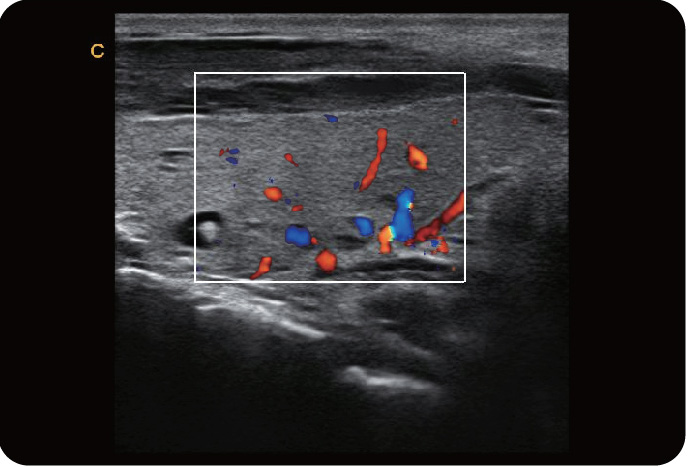

脐动脉,C模式

颈动脉,C模式